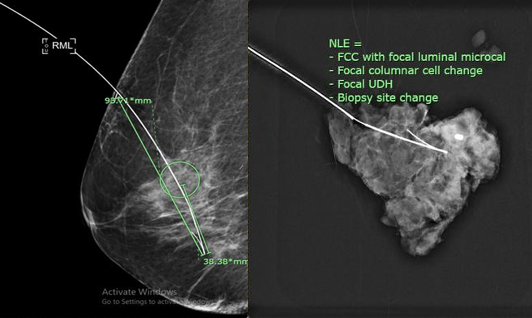

Needle localization under mammographic guidance

Sicha Cherdkiattikul, Jirapa Nuanchom, Chaiwat Cherdkiattikul

89-100